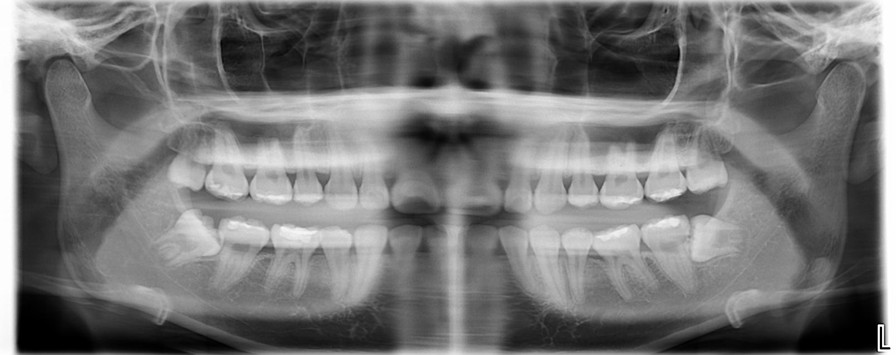

環口X光檢查

治療前,環口X光檢查,#38牙齒位不正